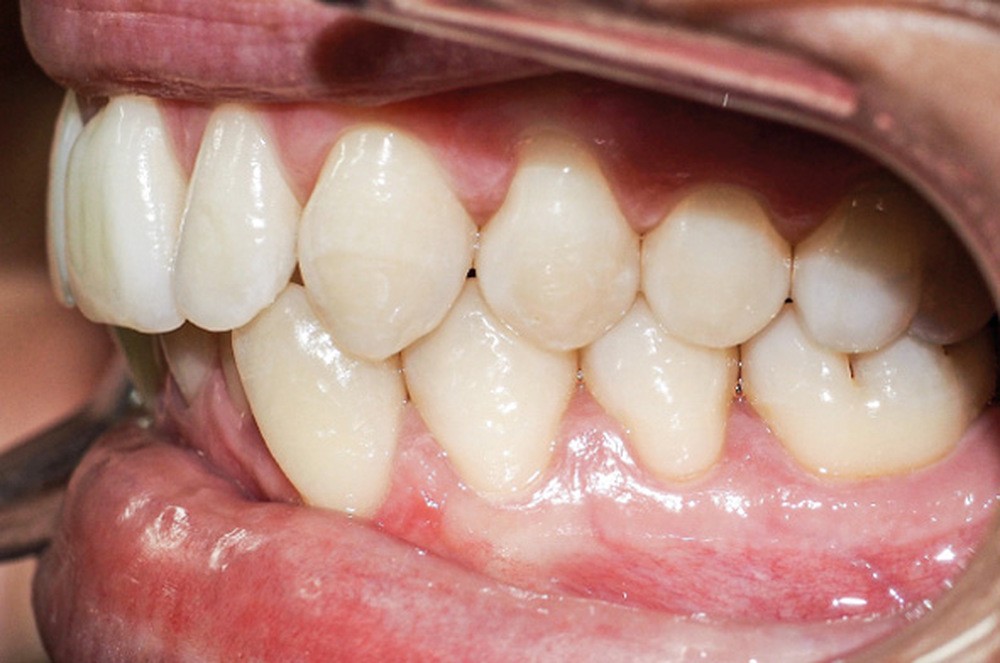

Discussion (fig. 4 à 7)

La durée du traitement a été de vingt-trois mois. Des mouvements lents ont permis un contrôle des axes incisifs mandibulaires.

Le stripping maxillaire a permis :

- de rééquilibrer les dimensions entre les incisives centrales et latérales (DDD initiale par insuffisance maxillaire) ;

- d’éviter l’apparition de triangles noirs entre les incisives [3] ;

- d’éviter la présence d’un surplomb résiduel.

Des triangles noirs sont apparus à la mandibule suite à l’extraction de 31 : ils ne sont pas exposés lors du sourire, ce qui n’entraîne pas de défaut esthétique.

La génioplastie discrète apporte un équilibre facial et une fermeture labiale non forcée, ce qui limite le risque de récidive liée à la pression musculaire.

La superposition des structures anatomiques nous montre une ingression de l’incisive mandibulaire et un maintien de l’axe ainsi qu’une distalisation en gression de l’incisive maxillaire.